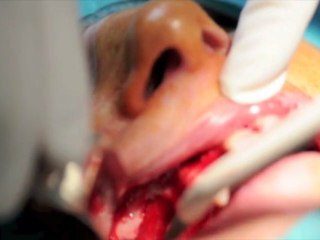

Retinal Detachment

Mr Mahi Muqit PhD FRCOphth is a Consultant Ophthalmologist, Cataract and Vitreoretinal Surgeon at the world famous Moorfields Eye Hospital in London.To more information please visit us .